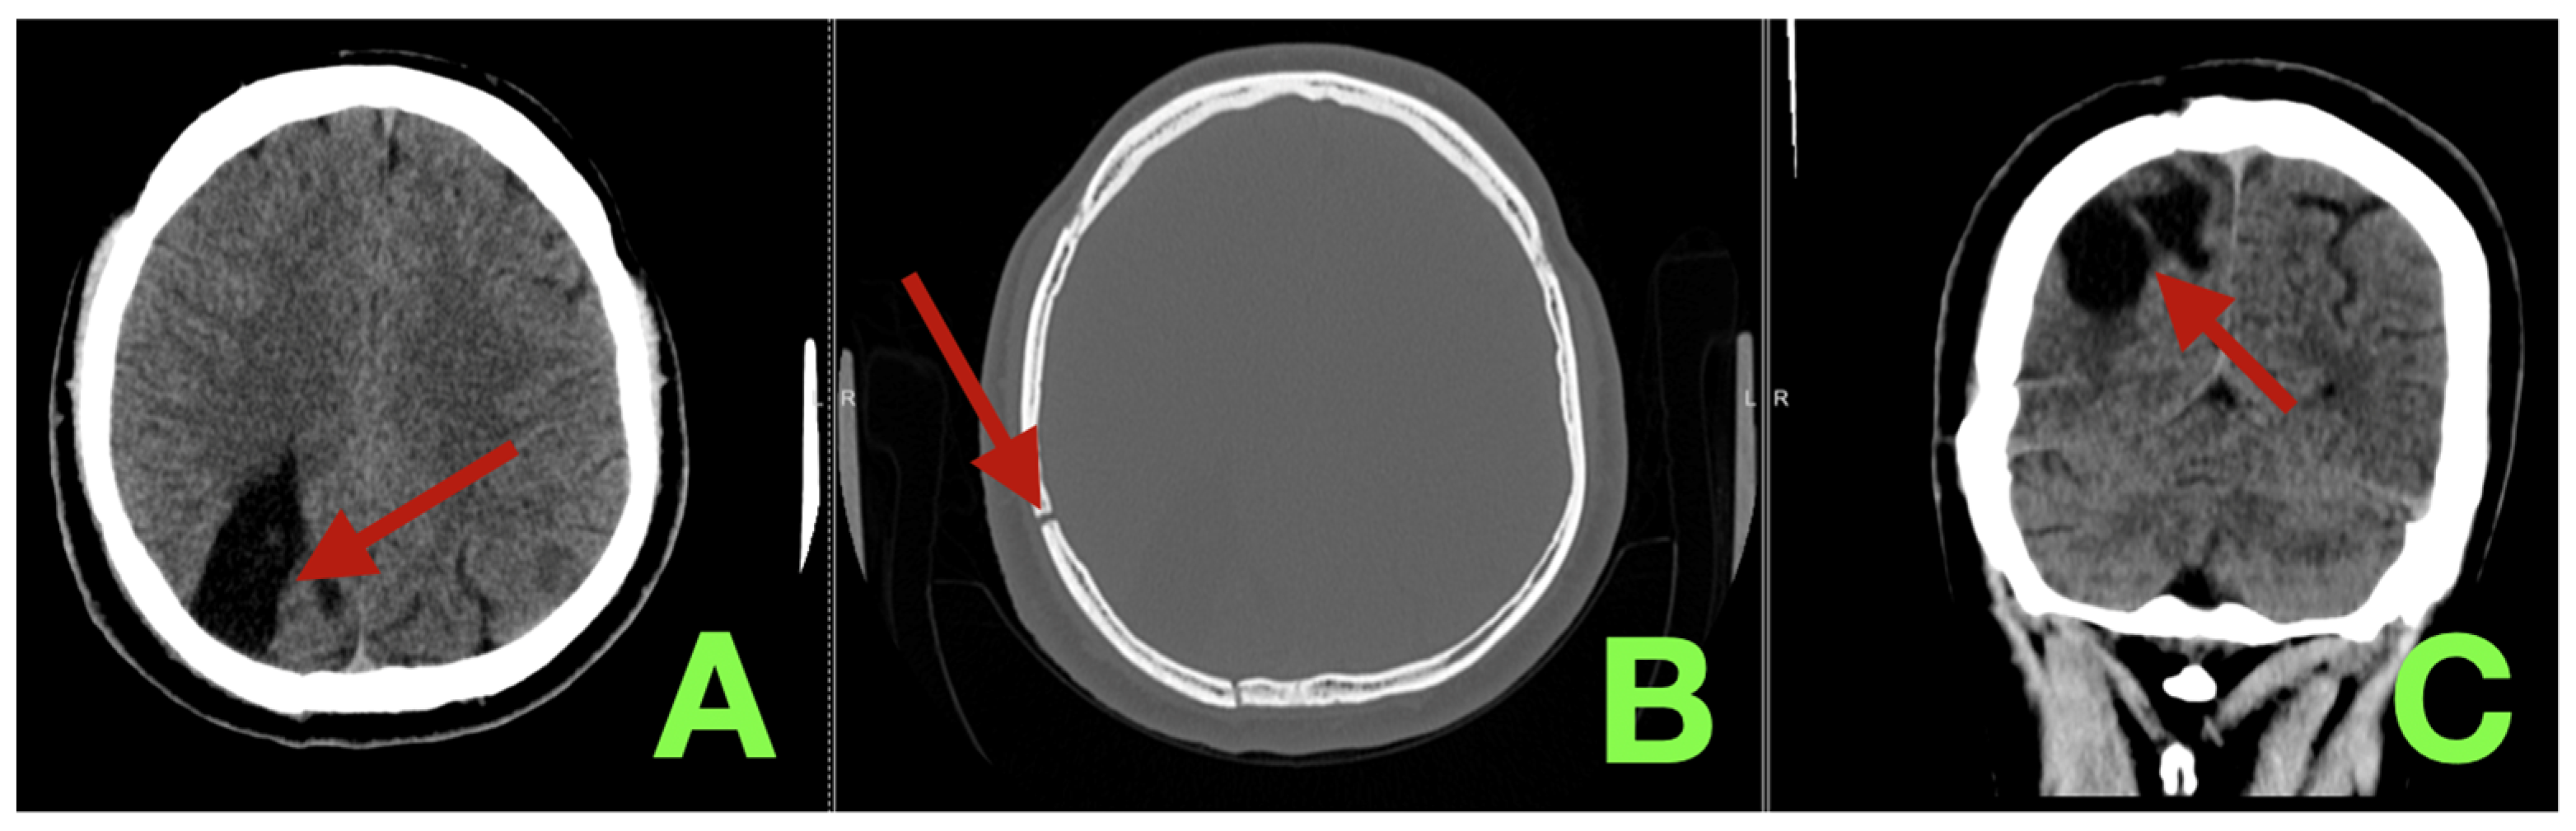

2. Case Presentation